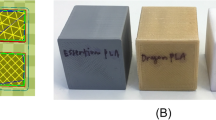

A total of 192 rectangular models (40 mm × 8 mm × 3 mm, Audoesk Fusion 360®) were designed and printed using the FFF-PLA system (Eryone Filament PLA White®) with the parameters defined in Table 2 and with an infill percentage of 30%, which was the highest infill percentage used in our study (Cura Ultimaker®, Utrecht, The Netherlands).

The main limitation of the present study is that is only focuses on one parameter, namely infill percentage, of the many that can be configured to increase the thermal resistance of biomodels. In some cases, a lower infill percentage could be adequate if, for example, the number of external layers or the wall thickness were greater, specially in small bones whereby the infill area is very small. The reason why we focused on infill percentage rather than on some other parameter had to do with the fact that infill is the main contributor to mechanical strength in large objects like biomodels, whereas wall thickness is a more important factor for smaller objects. The infill pattern is another important key part in the 3D printed biomodels and the optimal printing protocol could be quite different using other infill pattern. In our study, we selected the gyroid pattern due to its lightweight and our experience with it, but other infill patterns can be as useful as gyroid pattern with an adequate printing protocol. Future studies should analyze combinations of different parameters with a view to increasing thermal resistance. The protocol presented here is an effective alternative but by no means the only one. However, it is probably the most effective alternative so far reported in the literature.